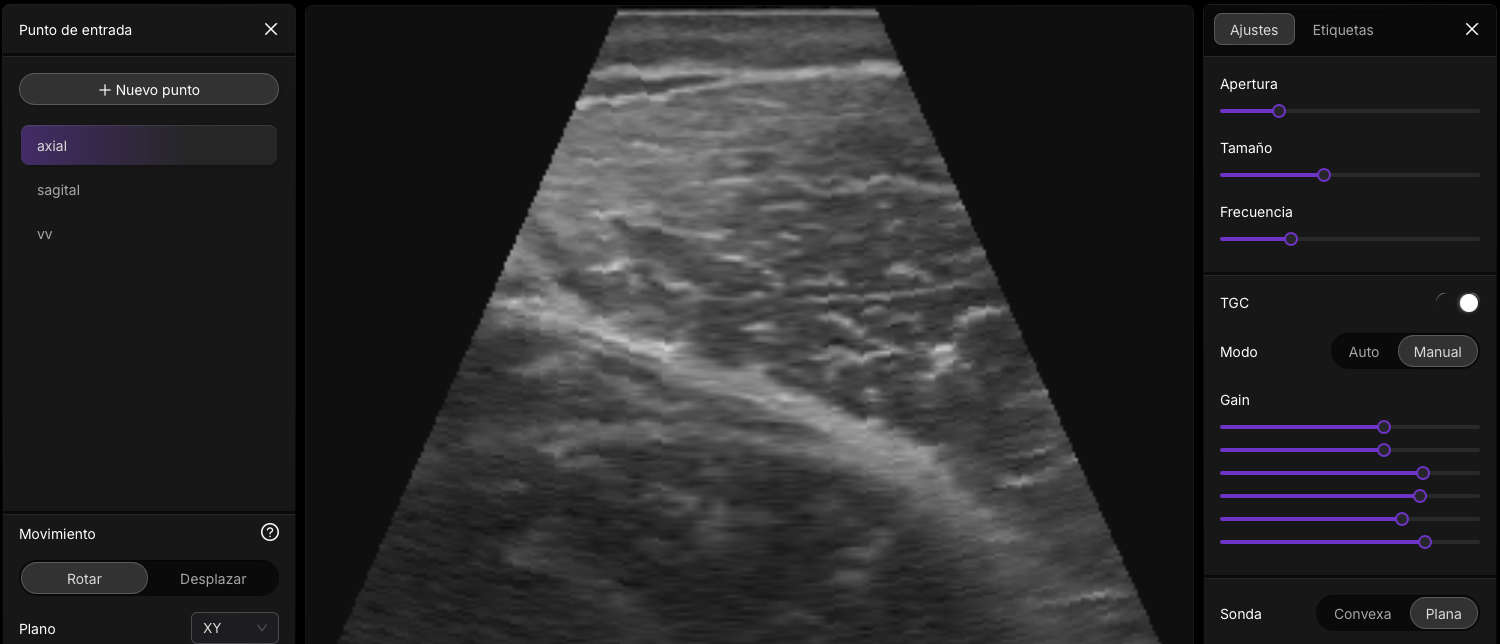

El comportamiento de los ecos es un aspecto fundamental en la ecografía, ya que define cómo las ondas de ultrasonido interactúan con los tejidos y cómo se forman las imágenes. La interacción entre el ultrasonido y los tejidos varía en función de la orientación de la interfaz, la suavidad o rugosidad de las superficies y las características de los tejidos, como la impedancia acústica. Esta sección explora el comportamiento de los ecos en situaciones de incidencia perpendicular y oblicua, así como el fenómeno de la dispersión.

Ecos Perpendiculares

Cuando el haz de ultrasonido incide perpendicularmente sobre una interfaz lisa entre dos tejidos, una parte de la energía sonora continúa en la misma dirección y se transmite al segundo medio, mientras que otra parte se refleja en dirección opuesta. La proporción de energía reflejada depende directamente de la diferencia de impedancia acústica entre los dos medios. A mayor diferencia de impedancia, mayor será la cantidad de energía reflejada y, por lo tanto, mayor será la intensidad del eco.

La impedancia acústica (medida en rayls) de un tejido es un factor que depende de la densidad del tejido y la velocidad del ultrasonido en ese medio. La relación entre la impedancia de los tejidos determina tanto el coeficiente de reflexión de intensidad como el coeficiente de transmisión de intensidad. Estos coeficientes cuantifican la fracción de energía sonora que es reflejada y transmitida al pasar de un medio a otro.

Ecos Oblicuos

Cuando el ultrasonido incide en una interfaz con un ángulo oblicuo, el comportamiento de los ecos sigue principios diferentes. En este caso, el ángulo de incidencia es igual al ángulo de reflexión, lo que significa que la energía reflejada rebota en el mismo ángulo con el que llegó. Sin embargo, el ángulo de transmisión (el ángulo con el que la energía atraviesa la interfaz hacia el segundo medio) depende de la diferencia de impedancia entre los dos tejidos. A mayor impedancia en el segundo medio, el ángulo de transmisión será más inclinado; mientras que a menor impedancia, la transmisión tenderá a ser más perpendicular.

Este comportamiento sigue la ley de Snell, que en ecografía se aplica para calcular el cambio de dirección de la onda sonora al pasar de un medio a otro con diferente impedancia acústica.